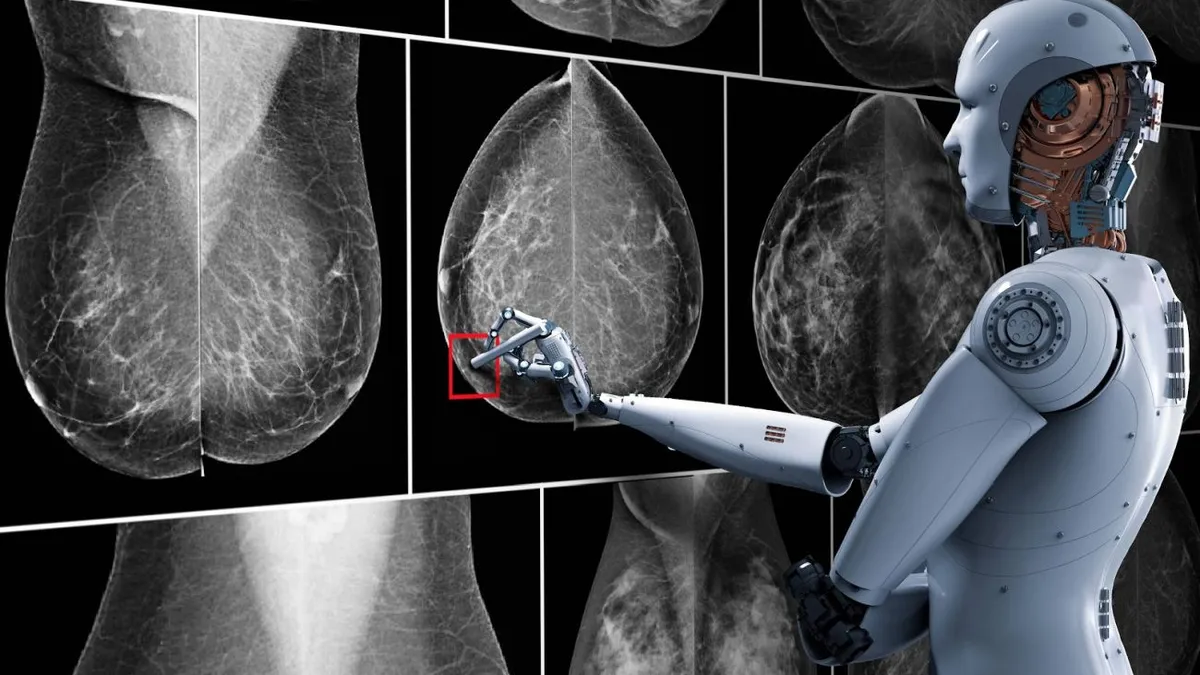

La herramienta Damo Panda podría revolucionar el diagnóstico precoz de una de las enfermedades oncológicas más letales

La división de investigación de Alibaba Group (NYSE), conocida como Damo Academy, ha logrado un importante reconocimiento por parte de la Administración de Alimentos y Medicamentos de Estados Unidos (FDA), que ha designado como «dispositivo innovador» a su herramienta de inteligencia artificial para la detección del cáncer de páncreas. Esta calificación especial permitirá a la tecnología china acceder a un proceso de revisión y aprobación regulatoria acelerado en el mercado estadounidense.

El modelo de IA, denominado Damo Panda (PANcreatic cancer Detection with Artificial intelligence), fue diseñado específicamente para identificar el cáncer pancreático en sus etapas iniciales, cuando aún no se han manifestado síntomas y las posibilidades de tratamiento efectivo son mayores. Según reporta el South China Morning Post, la herramienta utiliza técnicas avanzadas de aprendizaje profundo para analizar tomografías computarizadas abdominales sin contraste.

El sistema fue presentado por primera vez en noviembre de 2023 mediante un estudio publicado en la prestigiosa revista científica Nature Medicine. Los resultados iniciales son alentadores: tras ser entrenado con datos de más de 3.200 pacientes, Damo Panda demostró una sensibilidad 34,1% superior a la de radiólogos humanos en la detección de tumores malignos pancreáticos.

Alibaba ya ha comenzado a implementar ensayos clínicos en China, donde la herramienta ha examinado a aproximadamente 40.000 personas en un hospital de Ningbo. Durante estas pruebas, el sistema logró identificar seis casos de cáncer pancreático en etapa temprana, dos de los cuales habían pasado inadvertidos para los radiólogos durante los exámenes rutinarios.

En este contexto, tecnologías como Damo Panda representan una oportunidad sin precedentes para mejorar significativamente el pronóstico de los pacientes mediante la intervención médica temprana.

Diversos estudios, como el publicado en The Lancet Digital Health, han demostrado que los algoritmos de IA pueden igualar e incluso superar a los profesionales médicos en tareas específicas de diagnóstico por imagen. En algunas aplicaciones clínicas, estos sistemas han alcanzado niveles de precisión superiores al 90%.